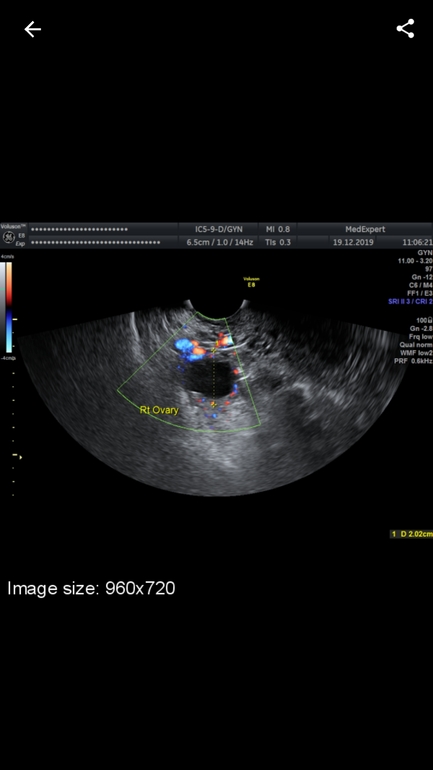

Ходила на узи ,там сказали что эндометрий 11 мм.

Желтое тело 20 мм .